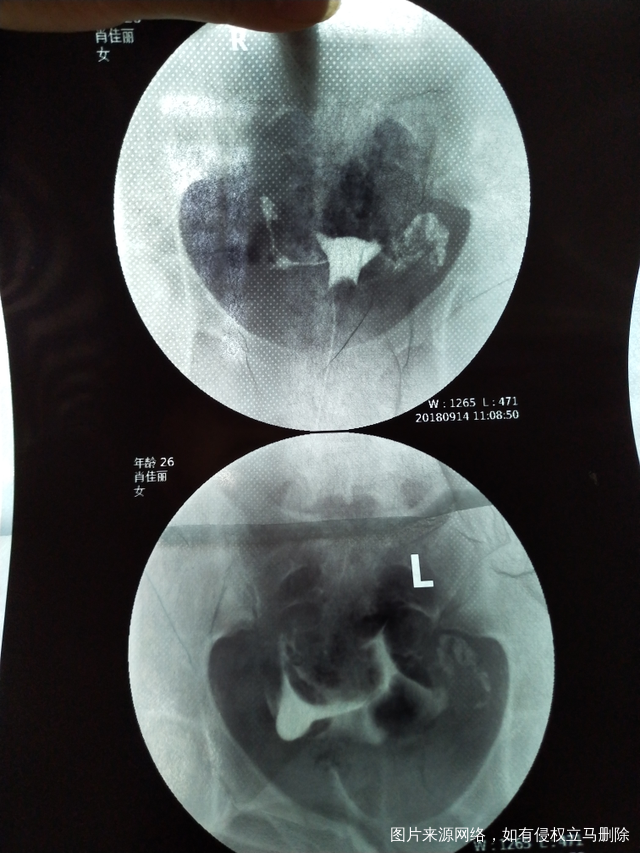

今天做了造影 医生帮我看下怎么样吧?